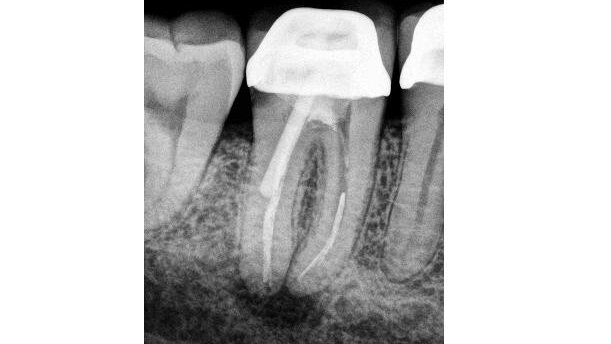

The key study referenced on the presence of microbes within the root in cases of persistent AP is Nair et al.[4] When considering the cause of the persistent infection, consider that the microbes were either present prior to RCT being initiated (primary infection) or they entered during or after treatment (secondary infection).[5] In considering those microbes that have survived from the primary infection, consider how they might have achieved this. They may have been resistant to the chemicals used in the disinfection process (Enterococcus faecalis, for example, has some mechanisms to survive calcium hydroxide), or they may have been located in a portion of the canal that was not instrumented nor cleaned via chemical means.

Regarding secondary infection, these microbes may have gained access to the canal during treatment or after treatment. Consider too that they may have been carried into the canal on a contaminated instrument or perhaps a leaking rubber dam may have allowed saliva to contaminate the root canal. Alternatively, a poorly placed temporary restoration may have allowed leakage into the root-canal system in-between visits. If caries has not been completely removed, or a previous restoration subject to micro-leakage is left in place, then this can also be a source of secondary infection. Alternatively, these microbes may have entered a previously clean root-canal system after the completion of RCT. This could be due to a leaking restoration, or through caries or a crack in the tooth. It is important to understand the microbial nature of AP, and to have this foremost in our minds when undertaking treatment.

When exogenous materials are located in the periapical region, they can induce and maintain an inflammatory response, which may be asymptomatic, but will be seen as a radiolucency. Materials may be gutta-percha, amalgam, sealants, calcium hydroxide or cellulose fibres, such as those contained in paper points.[17]

Gutta-percha may also induce a foreign-body reaction, especially in fine particles.[18] Overextended gutta-percha may, as a result, cause delayed healing of periapical tissue.